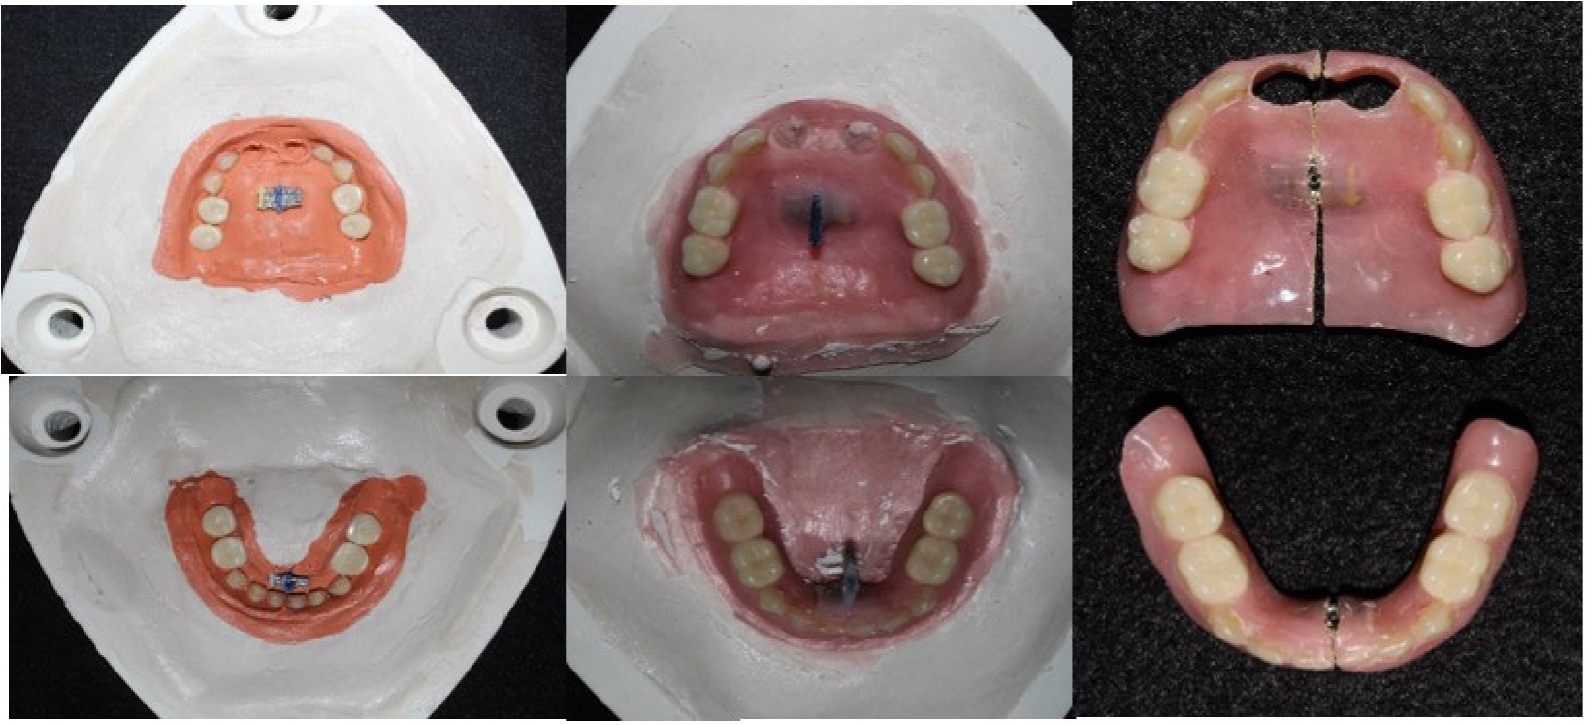

El tratamiento odontológico se inicia con impresiones de alginato (Tropicalgin de Zhermack), obtención de modelos y elaboración de cubetas individuales, posteriormente se realizó la impresión funcional con silicona (Body ExpressTM STD de 3M ESPE). Se obtuvo el modelo de estudio sobre el que se elaboró la base con rodillos de cera, realizándose posteriormente las pruebas de ellas en el paciente (Figura 4) y se articuló en verticulador. Se realizó la articulación de dientes de acrílico anteriores y posteriores (Figura 5), se realizó prueba de dientes en el paciente. Posteriormente se colocaron los tornillos de expansión en la prótesis superior e inferior y se procesaron las prótesis en el Laboratorio de Prótesis Bucal Avanzada de la ENES León de la UNAM (Figura 6).

Figura 4: Prueba de rodillos de cera.

Figura 5: Colocación de dientes de acrílico.

Figura 6: Procesado de prótesis removibles